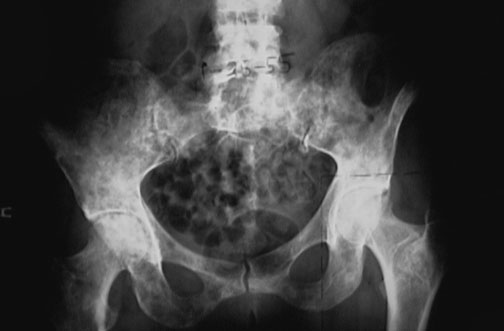

This radiograph demonstrates many osteolytic metastases in the pelvis in a patient with metastatic breast carcinoma.